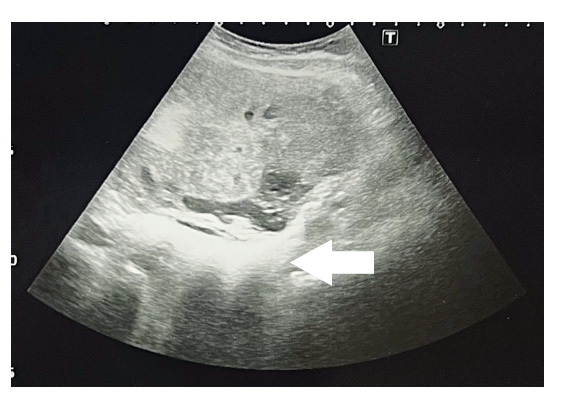

Figura 3 Hiperecogenicidad placentaria y heterogeneidad, hiperecogenicidad de placa corial.

Los hallazgos ecográficos más llamativos son la localización anormal de la placenta, hiperecogenicidad y heterogeneidad a la escala de grises en diversas zonas placentarias, parénquima placentario muy diferente al que estamos acostumbrados cuando observamos placentas normoinsertas 17). Por otro lado, se puede evidenciar modificaciones anatómicas de la placa basal y de la placa corial en la ecografía, producto de un proceso neoproliferativo que afecta toda la placenta en forma focal, parcial o total 18). Y la sombra que la acompaña es la presencia de lagunas vasculares de bordes irregulares, que no solamente tienen manifestaciones en la escala de grises sino, más bien, en el flujo aumentado en la placenta al medir con la flujometría Doppler. Estos hallazgos son sugerentes de acretismo 18,19).

La determinación ecográfica de la hiperecogenicidad placentaria heterogénea, placa corial hiperecogénica irregular (aspecto despulido) y la velocidad máxima del flujo Doppler (cm/seg) representan parámetros útiles de aporte al diagnóstico de acretismo placentario.